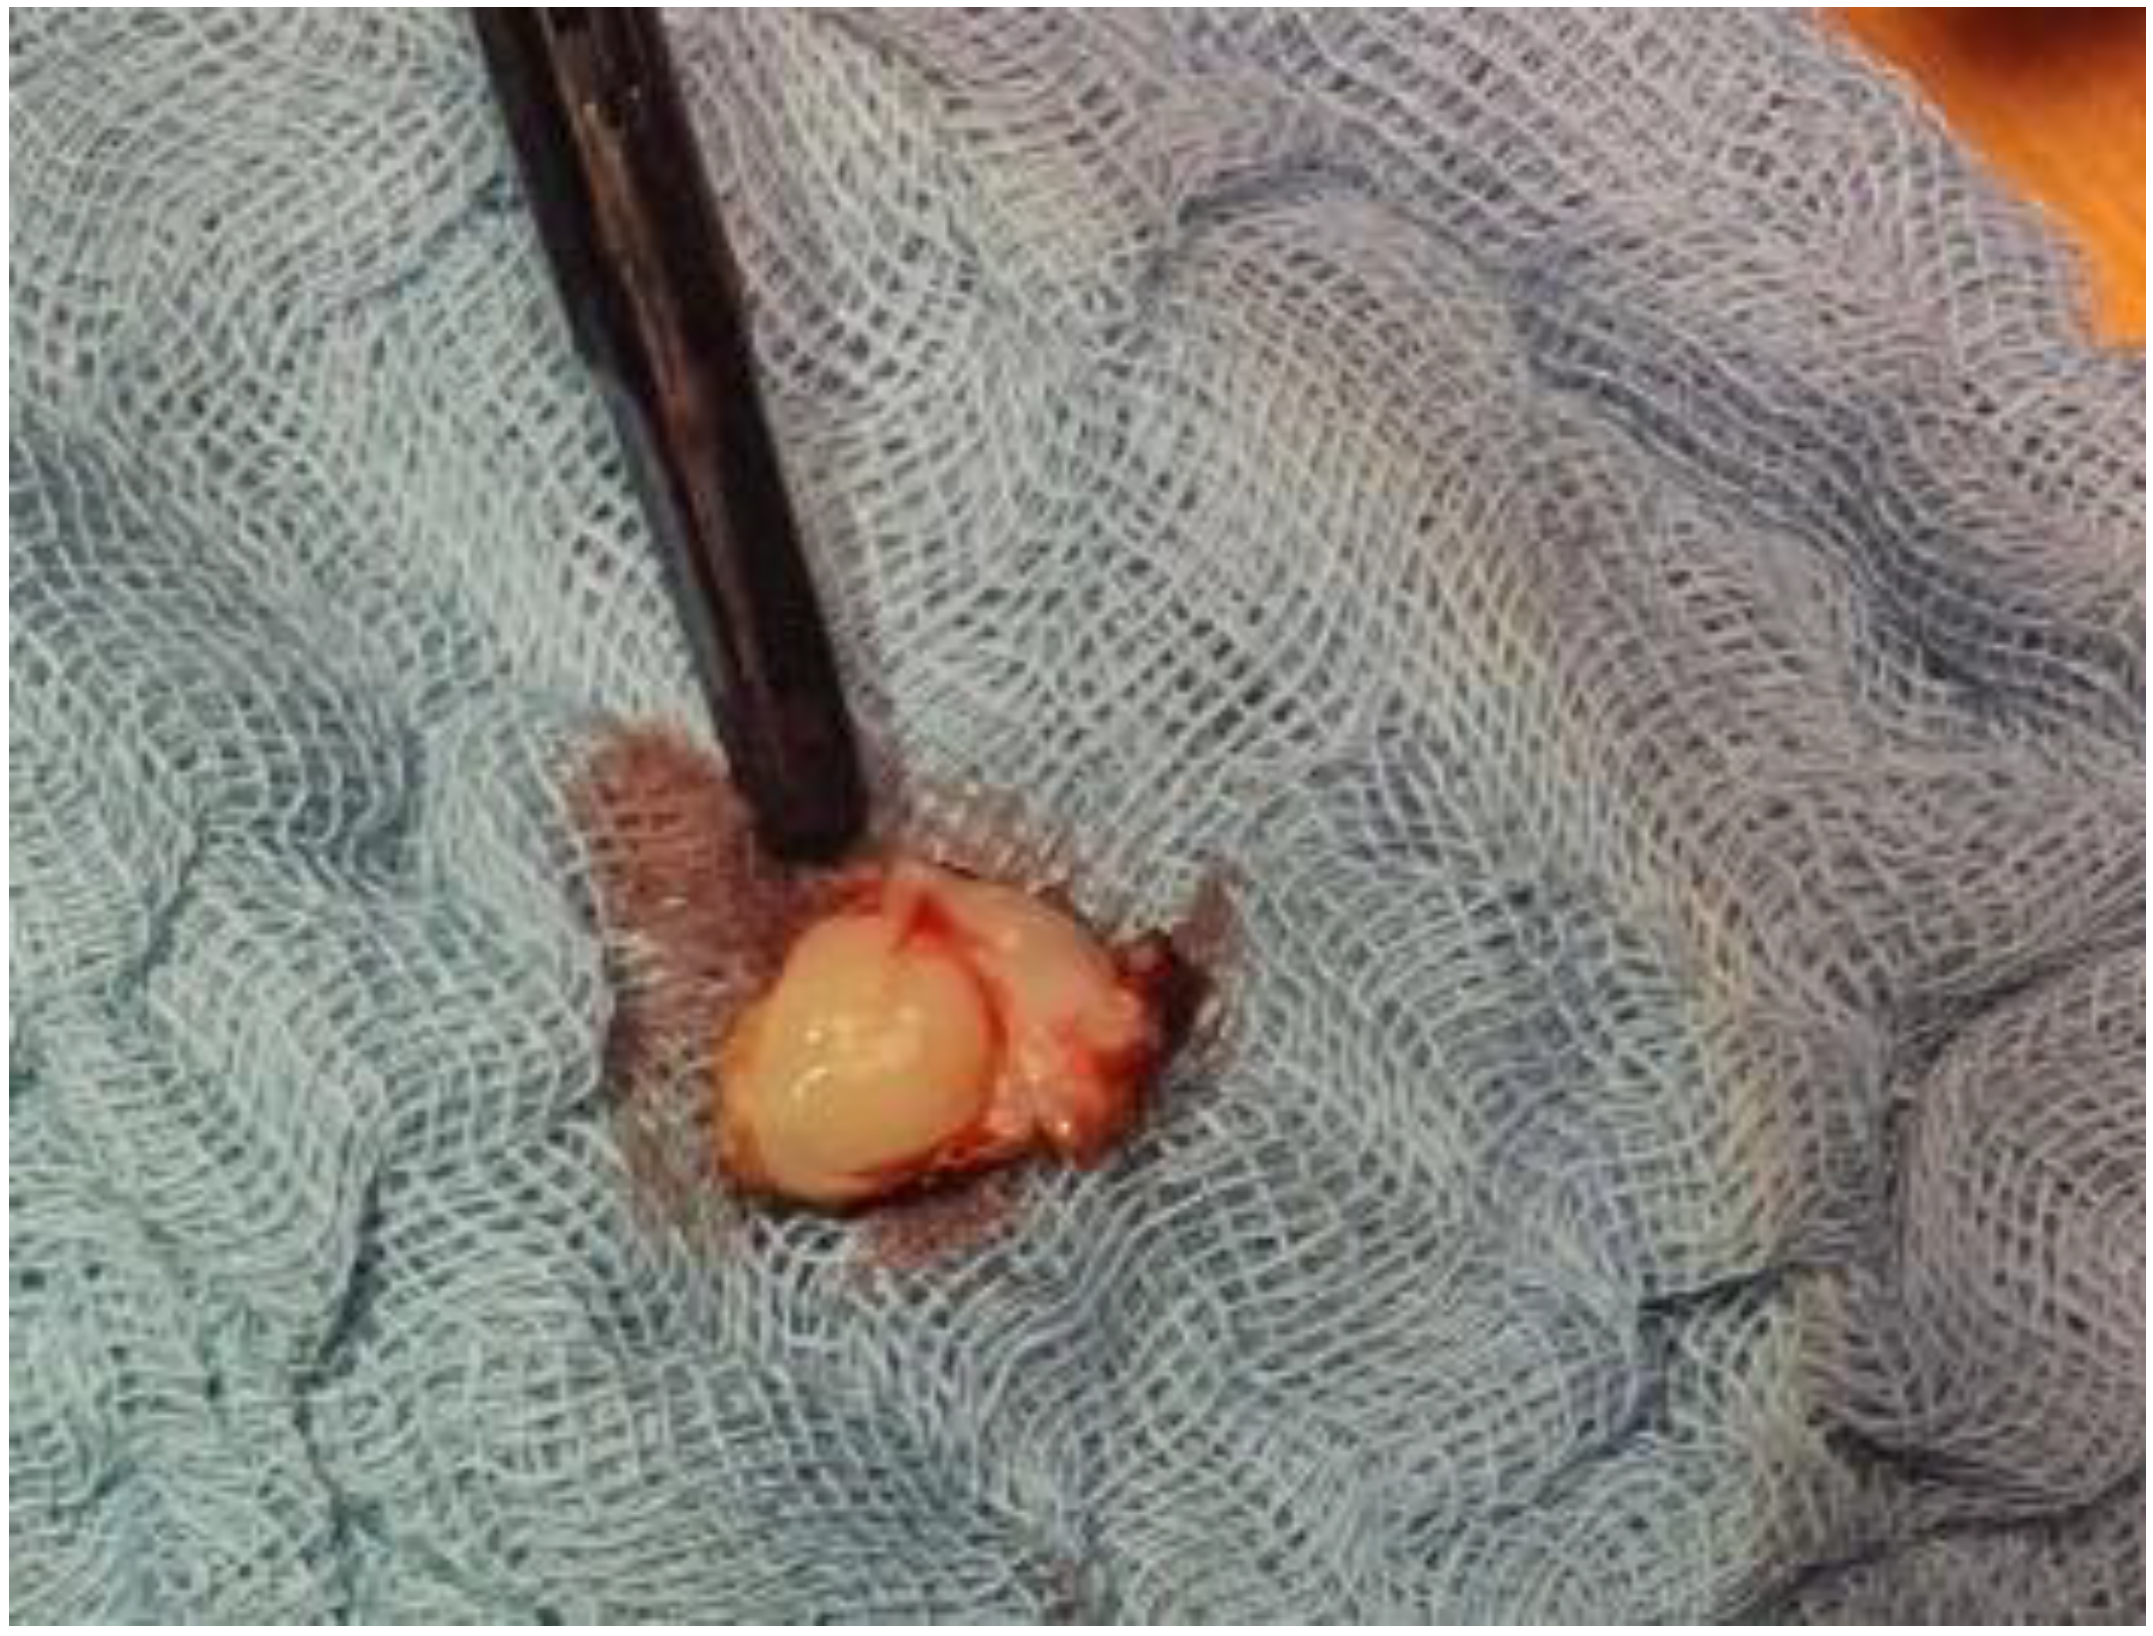

2. Case Report